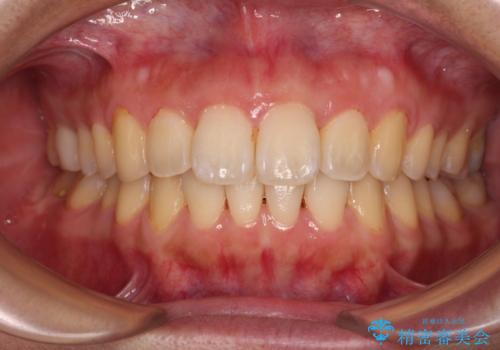

[ インビザライン矯正 ] マウスピースで治す前歯のがたつき

担当医 大元洋佑

![[ インビザライン矯正 ] マウスピースで治す前歯のがたつきの症例 治療前](https://seimitsushinbi.jp/wp/wp-content/uploads/2023/11/C7-500x350.jpg?v=1699665009)

![[ インビザライン矯正 ] マウスピースで治す前歯のがたつきの症例 治療後](https://seimitsushinbi.jp/wp/wp-content/uploads/2023/11/IMG_2993-500x350.jpg?v=1699664953)